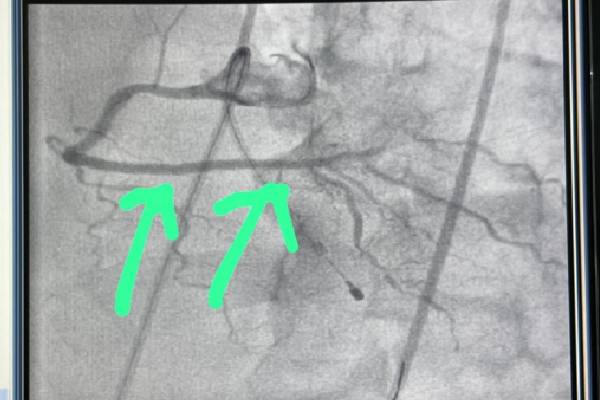

Angioplasty for Distal RCA 80-90% Stenosis

Below are the images showing the distal RCA before and after the angioplasty. The dramatic improvement after the blockage was cleared highlights the effectiveness of the treatment.

Before

A 60-year-old male patient presented with recurring chest pain and shortness of breath. After a detailed diagnostic workup, it was discovered that the patient had 80-90% stenosis (blockage) in the distal Right Coronary Artery (RCA), significantly restricting blood flow to the heart.

Dr. Kartik Bhosale, a renowned Interventional Cardiologist in Pune, recommended angioplasty to treat the blockage and prevent further complications like heart attack. Three days ago, Dr. Bhosale performed a successful angioplasty, clearing the blockage and placing a stent to restore blood flow.